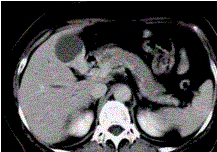

问题 患者女,50岁,右上腹痛,向肩胛部放射,伴有消瘦、乏力。查体:皮肤巩膜黄染,墨菲(Murphy)征阳性。CT示胆囊壁不规则增厚(下图)。 该病CT增强检查的表现为

选项 A.持续明显强化趋势 B.斑片状强化 C.呈“快进快出” D.延时期强化 E.未见明显强化

答案 A